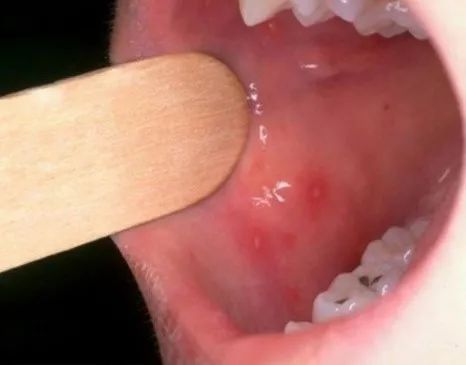

肠道病毒|手足口病、疱疹性咽峡炎夏秋季高发,家长需注意!

是肠道病毒引起的常见传染病